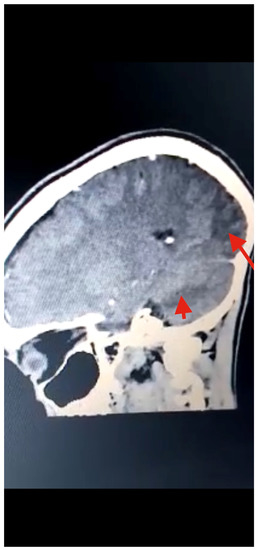

Figure 3.

Head CT scan showing multiple T1W hypointense, with T2W and FLAIR hyperintense, areas in the posterior and parietal cortices, indicative of infarction (red arrows) due to stroke from cysticercal invasion of the vascular bed.